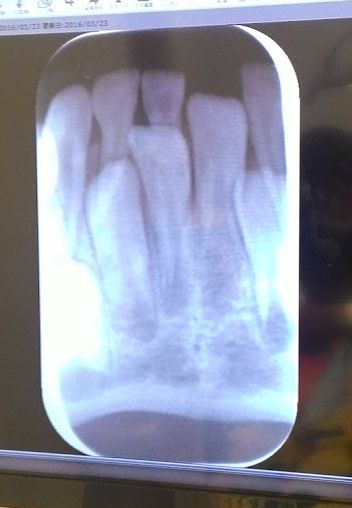

うしろの歯が生えてきたから連れて来たと言ってるんだし

先生も生えてきてますねと言ったのに

「一応レントゲンとりましょう、もし歯が生えてないと大変なので」といって

レントゲン撮られた。

永久歯かなりあがってきてるので、

前歯2本の隣2本も時間の問題って感じ